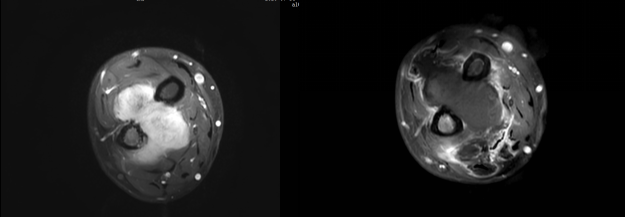

患者3年前無明顯誘因下出現(xiàn)右前臂腫脹,伴壓痛,程度不劇,至當(dāng)?shù)蒯t(yī)院就診,查MR提示:右前臂軟組織腫塊。遂行手術(shù)。術(shù)后病理示:右腕部梭形細(xì)胞腫瘤或瘤樣病變,結(jié)合免疫組化及影像學(xué)結(jié)果,考慮侵襲性纖維瘤病。2年前患者無明顯誘因下出現(xiàn)右前臂腫脹,隱痛,夜間加劇,伴皮溫升高,遂至我院就診,超聲提示右前臂尺橈骨間腫塊,考慮復(fù)發(fā)可能。患者行腋窩局部神經(jīng)阻滯下HIFU治療,術(shù)后復(fù)查腫塊消融約90%。

侵襲性纖維瘤 治療前MRI增強(qiáng),治療后1天MRI增強(qiáng)